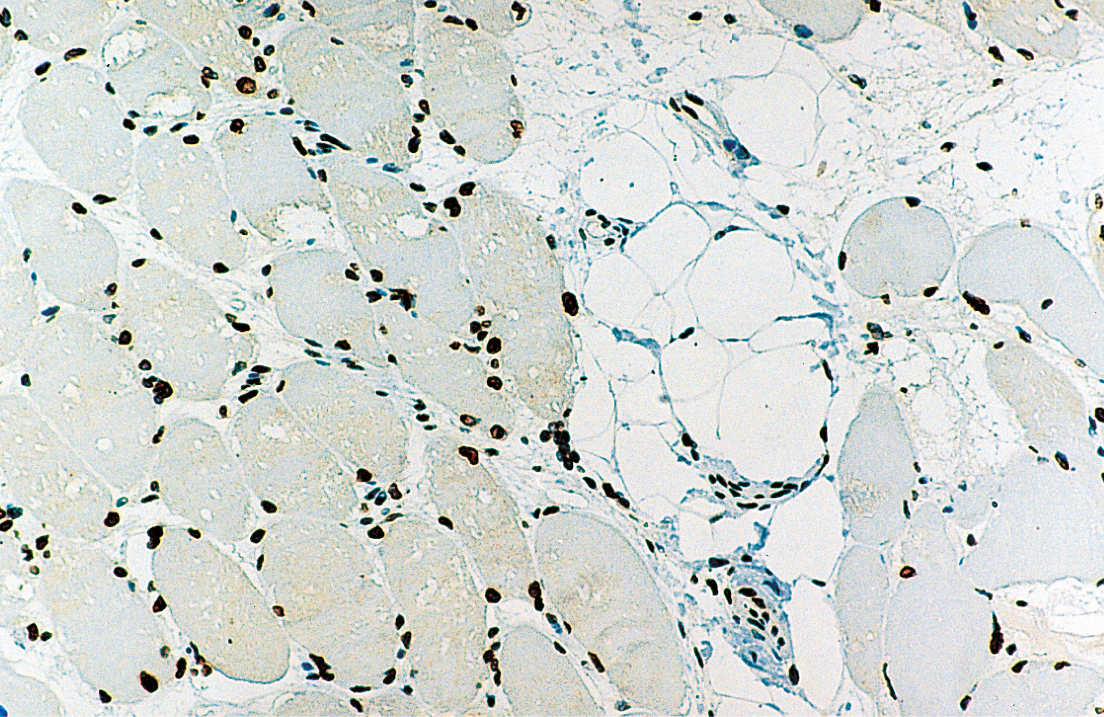

The HER2 antibody (BMA clone) was raised to a synthetic peptide corresponding to a region of the c-terminus of the mature HER2 protein attached to a carrier protein, Bovine Serum Albumin (BSA). Recommended on formalin-fixed paraffin-embedded tissue. The recommended epitope retrieval is a low-pH epitope retrieval solution.